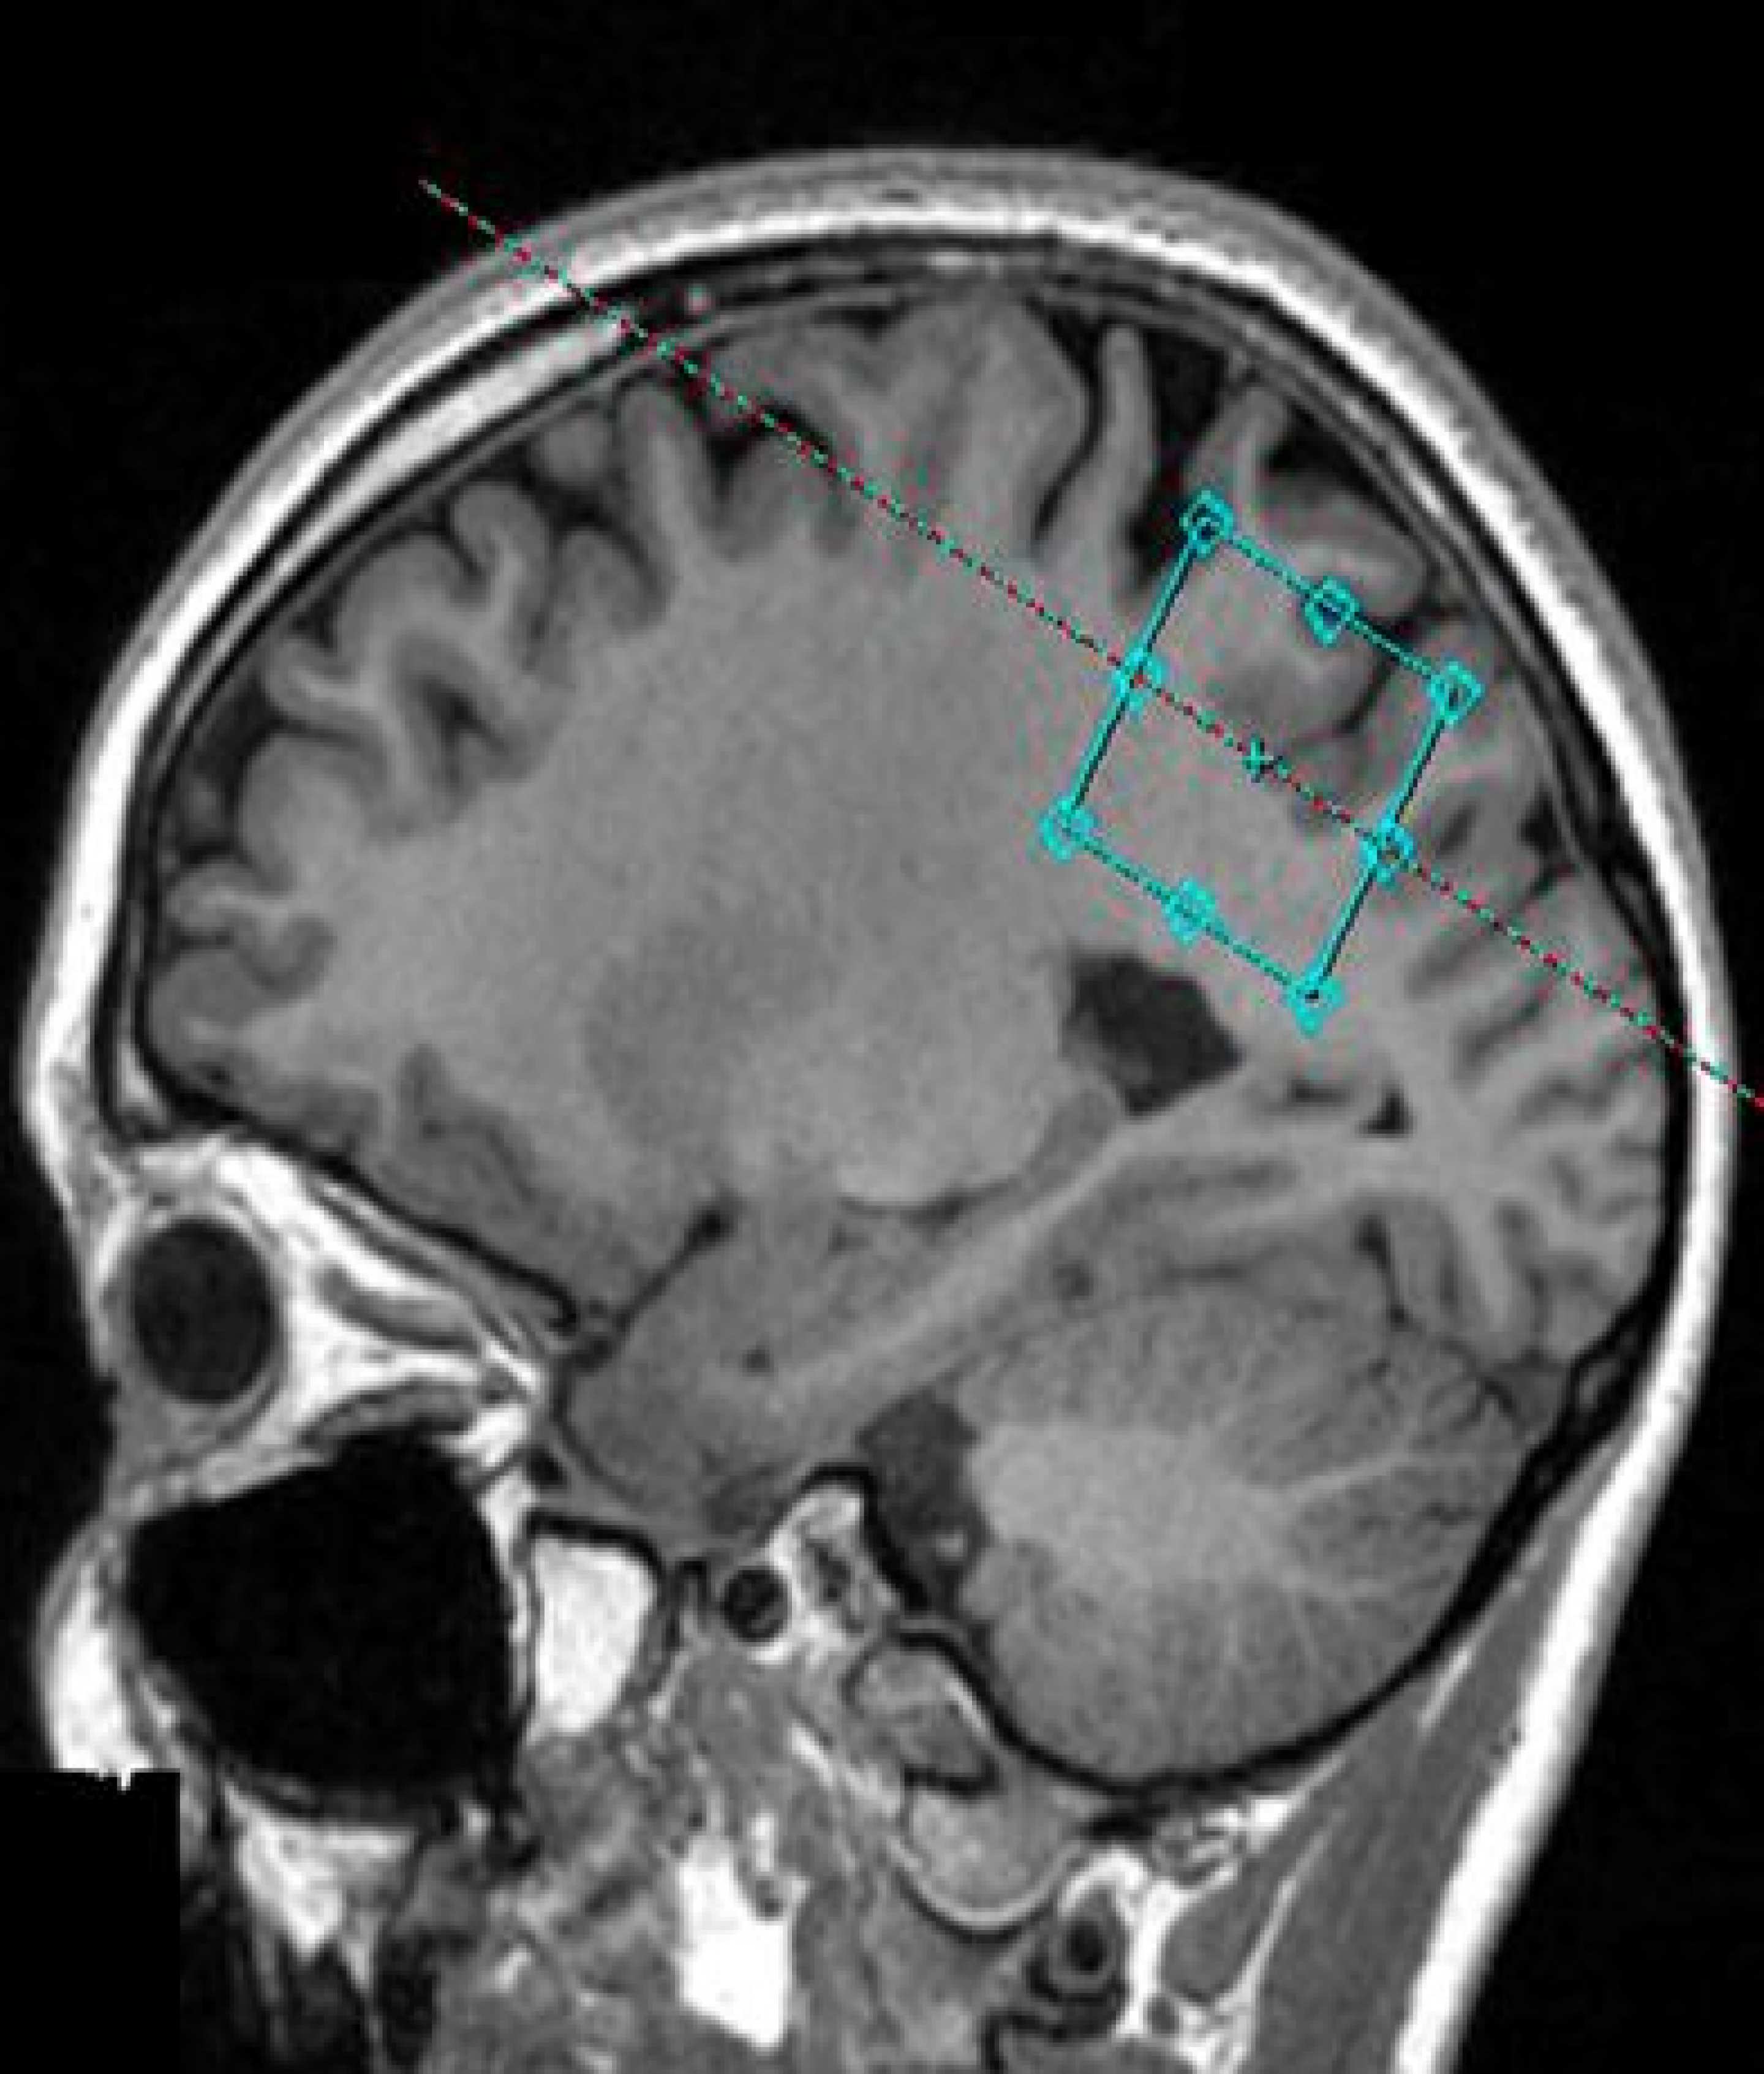

MRI brain scan indicating area of the brain where GABA is measured

A new study, published in NMR in Biomedicine, reveals higher levels of the chemical gamma-aminobutyric acid in the brain of migraine sufferers, supporting the theory that migraines are linked to a chemical imbalance in the brain.

Gamma-aminobutyric acid or GABA as it is commonly known, is the most abundant inhibitory brain chemical and has long been suspected to play a role in migraines due to its ability to influence pain. This study is the first to accurately measure GABA levels in the living brain.

The study compared the levels of GABA in twenty chronic migraine sufferers to an age and gender matched control group who did not experience any form of regular headaches. Brain scans were conducted when the participants were not having a migraine.

The measurement of GABA levels in the brain was made possible by a novel spectroscopy technique associated with MRI developed by researchers at the University of Sydney Brain and Mind Centre.